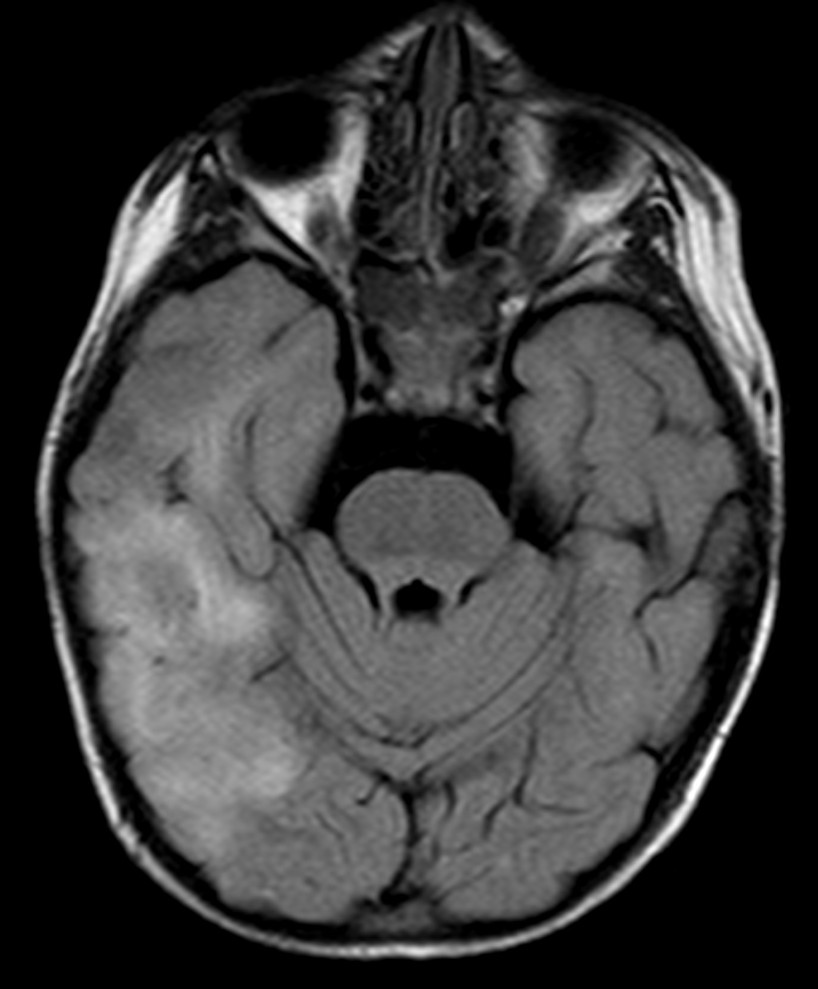

- Secuencias potenciadas en T2 y FLAIR muestran lesiones hiperintensas, de afectación bilateral, irregular, mal definidas, de tamaño variable y asimétricas que son la expresión de áreas de inflamación y desmielinización de la sustancia blanca. Las lesiones afectan sobre todo a la sustancia blanca cerebral, pero también a la sustancia gris y núcleos de la base y a médula espinal.

Las localizaciones cerebrales más frecuentemente afectadas son la sustancia blanca profunda (frontal y parietal sobre todo), sustancia blanca yuxtacortical, sustancia blanca periventricular, cuerpo calloso, sustancia gris cortical, tronco del encéfalo y cerebelo.

Las lesiones infratentoriales (incluyendo el tronco del encéfalo y la sustancia blanca cerebelosa) y las lesiones medulares son comunes, de ahí que algunos autores denominan según el área afecta encefalomielitis, cerebelitis o mielitis, siendo consideradas todas ellas variantes topográficas de una entidad común. Por ello, si no se ha realizado, es necesario realizar también una RM de columna.